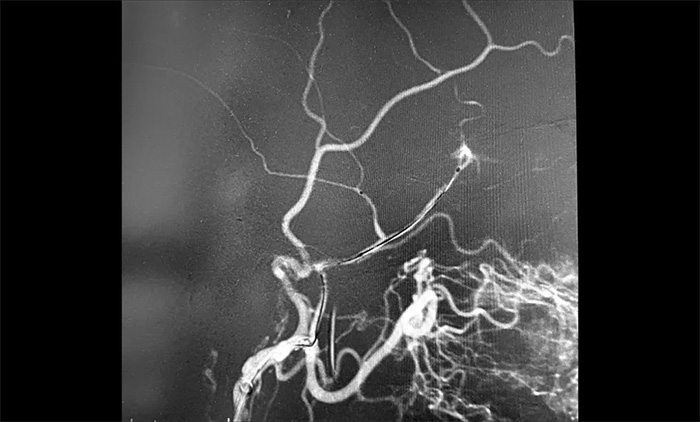

12月29日,順利進(jìn)行手術(shù)。術(shù)中,王貴平博士在介入團(tuán)隊(duì)協(xié)助下克服血管迂曲的困難,導(dǎo)管精準(zhǔn)到達(dá)左腦膜中動(dòng)脈前支、左腦膜中動(dòng)脈后支,之后緩慢注入液體栓塞劑,栓塞劑逐漸向腦膜中動(dòng)脈主干反流,復(fù)查造影,左腦膜中動(dòng)脈無明顯前向血流,手術(shù)成功。術(shù)后,患者無新發(fā)神經(jīng)功能缺損。言語不清,肢體活動(dòng)不利,頭暈等癥狀逐步好轉(zhuǎn)。

▲ 術(shù)中